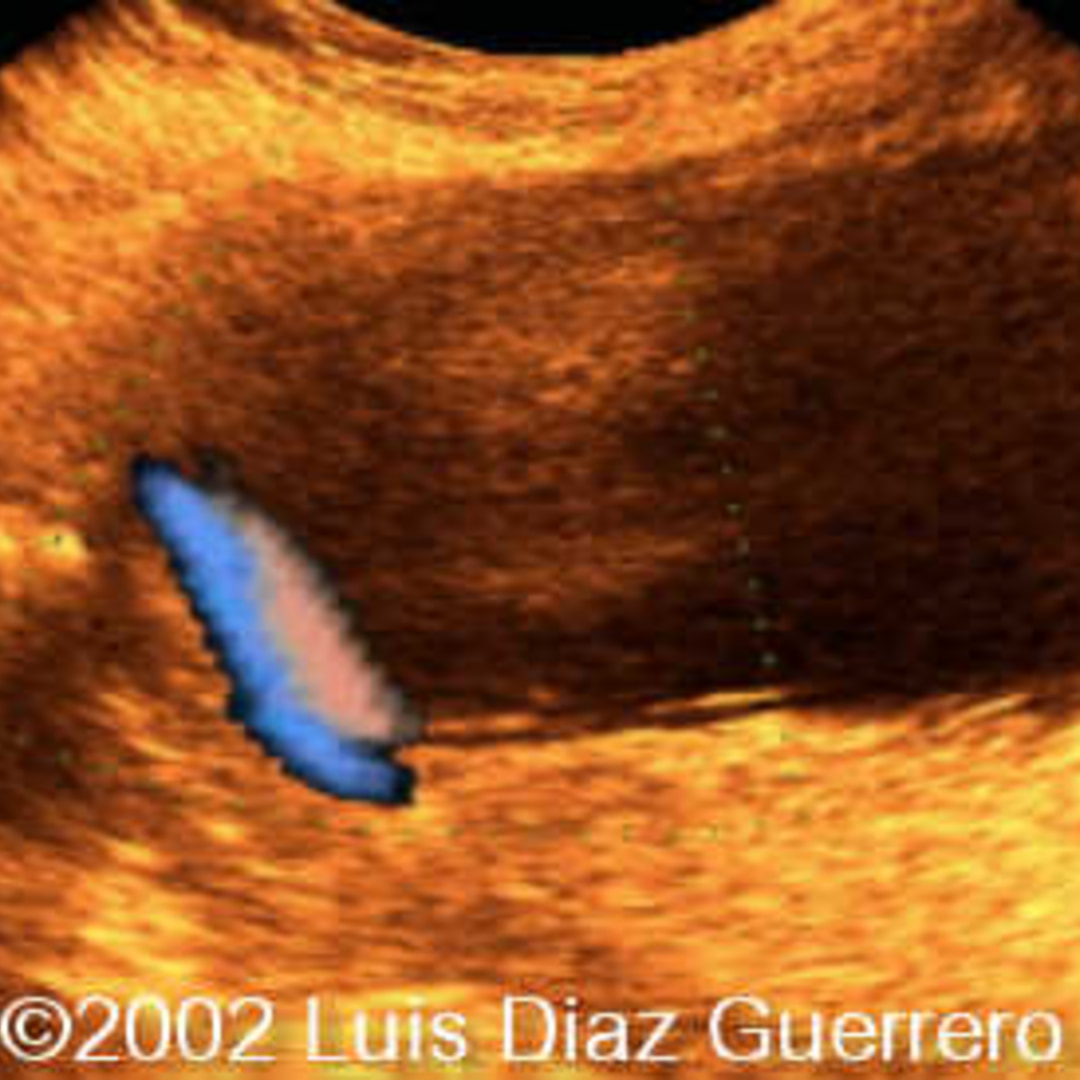

Velamentous insertion with vasa previa. (A, B) Colorflow Doppler Velamentous Cord Insertion Exercise Two types of vasa previa have been described. A velamentous cord insertion is when a fetus's umbilical cord abnormally inserts on the edge of the placenta along the chorioamniotic membranes. In a velamentous cord insertion (vci), the umbilical cord inserts into the fetal membranes (between the amnion and the. Unprotected fetal vessels in placental membranes and cord that are close. Velamentous Cord Insertion Exercise.